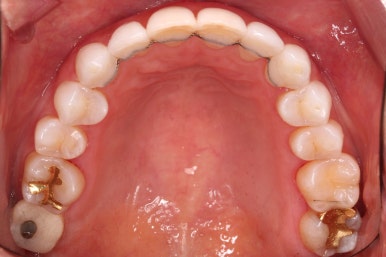

초진 시 입안의 모습입니다.

환자분이 원하셨던 부분은 윗니 작은 앞니가 하나 튀어나와서 개선하고 싶어하셨습니다.

부가적으로 아랫니 앞니가 마모가 심하여 높낮이가 달라보이는 점이었는데요.